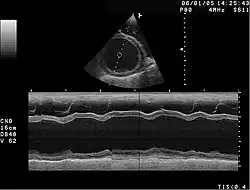

In der ursprünglichen rein "rechtsventrikulären" Form wurde beschrieben, dass mit dem Fortschreiten der Erkrankung immer mehr Muskulatur der rechten Herzkammer durch Fettgewebe ersetzt wird, wodurch sich die rechte Herzkammer vergrößert. Selten finden sich Einschränkungen in der Pumpfunktion des Herzens. Häufiger ist der bei körperlicher Belastung, wie beispielsweise Leistungssport, ausgelöste plötzliche Herztod (PHT) oder „Beinahe“-PHT, insbesondere bei jungen Menschen. Die Diagnose kann mittels Echokardiografie, MRT, EKG und McKenna-Score gestellt werden. Zur Behandlung kann ein Kardioverter-Defibrillator implantiert werden. Sportliche Belastungen sollten vermieden werden. Eine Herztransplantation ist in vielen fortgeschrittenen Fällen die Ultima Ratio.

Die Diagnose wird durch Echokardiografie, MRT oder Angiografie der linken Herzkammer bei einer Herzkatheteruntersuchung gestellt. Unklar ist der klinische Verlauf. Fälle von schwerem Herzversagen, Thromboembolie, Arrhythmien und plötzlichem Herztod sind bekannt. Familiär gehäufte Fälle wurden beschrieben, wobei Mutationen der Z-Scheibe, der Mitochondrien und des G4.5-Gens für Tafazzin isoliert werden konnten.[8]

Die dilatative Kardiomyopathie (DCM), bei der zunächst der linke Ventrikel (Herzkammer) (im Endstadium auch alle Herzhöhlen) erheblich erweitert ist (das Herz kann mit einem großen schlaffen Sack verglichen werden). Die Wandstärken sind meist nicht oder nur geringfügig verdickt (hypertrophiert). Das Herz zieht sich nur eingeschränkt zusammen (= systolische Funktionseinschränkung), oft kombiniert mit asynchronem Kontraktionsablauf der Kammern, bedingt durch eine Störung der Erregungsleitung infolge Linksschenkelblocks. Zahlenmäßig sind abgelaufene Herzmuskelentzündungen und chronischer Alkoholmissbrauch die häufigsten Ursachen. Es gibt auch angeborene Formen. Sekundäre Formen sind die „ischämische DCM“ infolge einer koronaren Herzerkrankung und der Endzustand eines Hochdruckherzens. Die DCM ist ein häufiger Grund für eine Herztransplantation, wenn der Zustand des Patienten mit Medikamenten, Koronarintervention oder kardialer Resynchronisationstherapie (CRT) nicht ausreichend gebessert werden kann. Die Diagnose wird nach klinischem Verdacht mit den typischen Symptomen durch bildgebende Verfahren (Echokardiografie, MRT, MSCT) und feingeweblich (Myokardbiopsie) gesichert. Eine koronare Herzkrankheit muss durch eine Herzkatheteruntersuchung ausgeschlossen werden, da sich hieraus eine kurative Behandlungsmöglichkeit der Ursache ergeben könnte.

Die restriktive Kardiomyopathie (RCM) stellt sich mit normal großen Herzkammern und einer meist normalen systolischen Pumpfunktion dar. Durch vermehrten Einbau von Bindegewebe in die Herzmuskulatur verhärtet die Herzmuskulatur. Die hierdurch versteiften Herzkammern lassen sich in der Erschlaffungsphase (Diastole) des Herzens schlecht füllen, das Blut staut sich in den Vorhöfen, die hierdurch stark vergrößert sind. Die Wanddicke der linken Herzkammer ist normal und die Herzklappen sind regelrecht.

Auffällig werden die Patienten durch Symptome einer Herzinsuffizienz wie belastungsabhängige Atemnot und Beinödeme. Die Erkrankung ist in den Industrieländern ausgesprochen selten und kann übersehen werden, wenn man nicht gezielt danach sucht. In tropischen Ländern ist die restriktive Kardiomyopathie hingegen weitaus häufiger und verursacht bis zu 20 % aller kardiovaskulären Todesfälle.[10] Diagnostische Methoden sind die Echokardiografie, gegebenenfalls mit Gewebedoppler, eine Herzkatheteruntersuchung mit Hämodynamikmessung, gegebenenfalls eine Herzmuskelbiopsie und eine MRT.